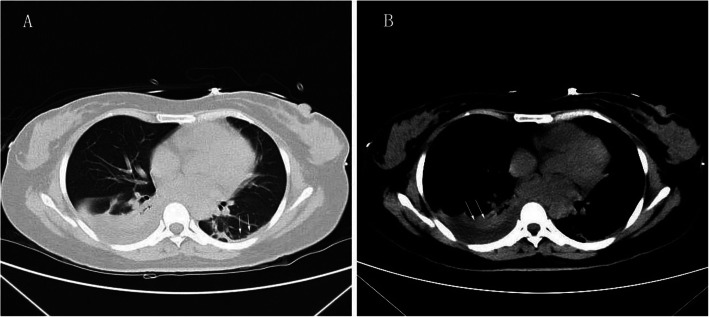

After LT, she received basiliximab and a methylprednisolone taper to induce immunosuppression; Mycophenolate sodium enteric-coated tablets, corticosteroids, tacrolimus for initial immunosuppression maintenance. The patient was extubated 18 h after surgery. On post-op day 5, a lung CT showed left pleural thickening and right pleural effusion (Fig. 1). On post-op day 6, no obvious improvements in her laboratory tests were evident, a liver angiography showed that the blood vessels were functioning but with delayed right hepatic perfusion (Fig. 2). Thus, low-molecular-weight heparin was used to anti-coagulate the blood. By post-op day 20, the patient’s allograft function had gradually improved. Then, the anti-TB regimen was changed to linezolid (LZD) at 0.6 g/day, levofloxacin at 500 mg/day, and pyridoxine at 100 mg/tid orally according to the recommendation of a TB expert. We modified the LZD according to blood concentrations. The histopathological examination showed submassive necrosis and cholestasis of the liver, which confirmed the diagnosis (Fig. 3). The foetus was managed by daily monitoring of the foetal heart rate. On post-op day 29, foetal sonography revealed mild bilateral ventricle widening, with the left side approximately 1.0 cm wide and the right side approximately 1.1 cm wide. The patient and her family decided to discontinue the pregnancy, providing ethical informed consent. Labour was induced via double balloon dilation for 12 h. On post-op day 30, the aborted foetus was vaginally delivered with spontaneous expulsion of the placenta, and the foetus had a normal appearance and weighed 280 g. A mother with active pulmonary TB can transmit the infection to her foetus, but the placental pathology of this patient was negative. The ultrasound scan indicated a possible incomplete abortion. On post-op day 37, we performed uterine curettage. The patient was then discharged. She has continued her anti-TB treatment and immunosuppression drugs as an outpatient. At the 3-month post-op follow-up, a routine chest CT revealed some ground-glass opacity nodules that turned out to be pulmonary aspergillosis, which responded to voriconazole (0.2 g/q12h for 14days). At the 8 months follow-up, the patient showed good general condition without TB relapse or liver damage.

Fig. 1.

Lung CT scan showing left pleural thickening and right pleural effusion